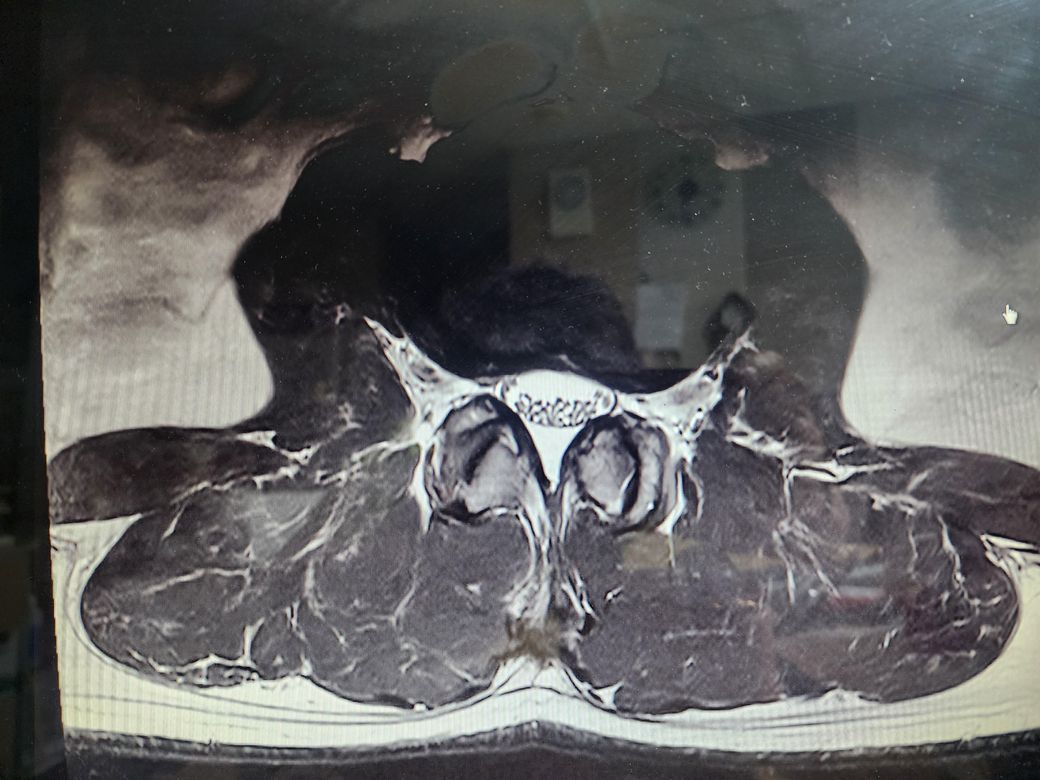

보여주신 MRI 상에는 척추관 협착증은 전혀 보이지 않습니다.

아래 첫번째 그림에 보시는것과 같이 B에서 보이듯이 검정색 신경뿌리 주변의 하얀색 뇌척수액이 공간 없이 비좁아지는 정도는 되어야 척추관 협착증이라고 이야기할 수 있을텐데 보여주신 MRI 에는 이런 모습은 없습니다.

정확하게는 제가 두번째로 올린 작성자분의 허리 MRI 사진중에서 빨간색 동그라미로 표시한 부분의 단면을 확인해야 더 정확한 설명이 가능하긴 하겠습니다.